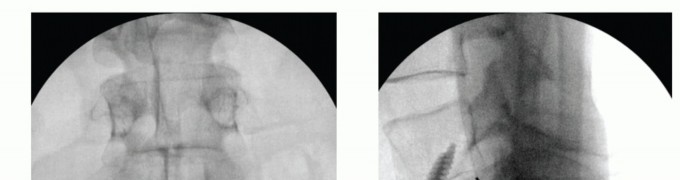

Once the discectomy has been completed, disc space distractors are inserted to gauge the size of the final implant (TECH FIG 3A). Appropriate distractor size can be gauged by comparing the operative level with a normal disc above or below. In addition, the interface between the distractor and the bony endplate should be less than 1 mm. This ensures good interference fit of the final device.

Endplate reamers are then inserted to appropriate depth as determined by lateral fluoroscopic imaging (TECH FIG 3B). Care should be taken to aim the reamer for the midportion of the disc space posteriorly on lateral fluoroscopy rather than through one endplate or the other.

- TECH FIG 3 • A. Lateral radiograph showing a radiopaque disc distractor within the intervertebral disc. The distractor approximates the height of the disc space above (L3-L4) and there is at most 1 mm of space between the intervertebral endplate and the distractor. B. Lateral radiograph showing reaming of the intervertebral channel for the anterior interbody device. Because the vertebral body is shallower in the AP plane away from the midline, reaming should stop shy of the posterior vertebral body line, as shown. C. Lateral radiograph showing threaded cage entry into the disc space. The cage is directed parallel to the vertebral endplates. (continued)

Final threaded implants are then screwed into the appropriate depth and orientation (TECH FIG 3C,D). The first cage (in a dualcage system) is inserted in the same trajectory as the reamers, and lateral fluoroscopic imaging during cage placement ensures that the cage is not placed too anteriorly or posteriorly. The cage should not be inserted beyond the depth of the reamer or else

- TECH FIG 3 • (continued) D. Final cage placement should not extend beyond the depth of the reamer. E. Lateral radiograph showing final cage placement. The overlapping pedicles confirm true lateral positioning. F. AP radiograph showing parallel positioning of paired cages.

The second cage is inserted using the first cage as a reference for trajectory and depth. Final images should be true AP and lateral projections showing the cage devices to be in good position. Overlapping pedicles on the lateral image will appear sharp, confirming true lateral positioning (TECH FIG 3E,F).

- TECH FIG 4 • AP (A) and lateral (B) fluoroscopic images showing midline positioning and screw trajectories of stand-alone ALIF device.

Typically, a single interbody cage that spans the disc space is selected, with graft material packed on both sides within the implant. This is positioned in the center of the interspace using product-specific instruments (TECH FIG 4A).

Locking screws are directed cephalad and caudad either through the cage device or through a metal faceplate that attaches to the cage (TECH FIG 4B). Knowledge of productspecific screw trajectories and starting points is paramount as they may be either symmetric about the midline or translated left or right to allow safe passage of the drill between the iliac vessels. - Adjunct Treatments